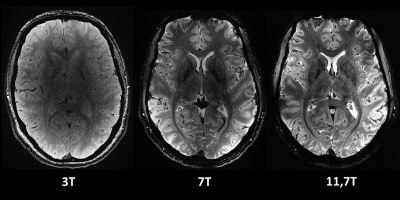

Crean el mapa más detallado del cerebro humano